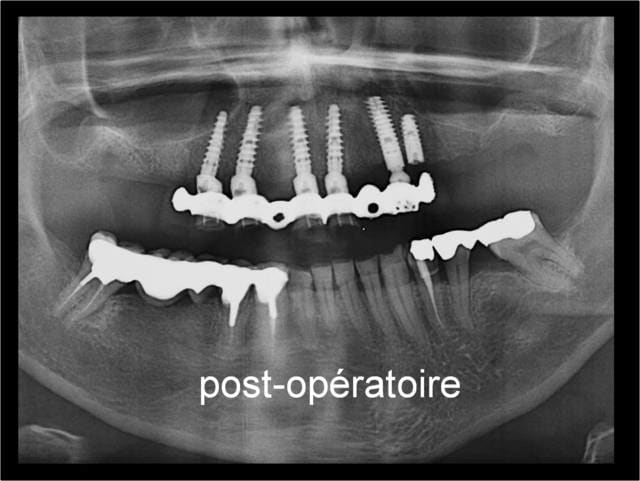

Patient d un pote chez qui on a pris l option décrite

1. poser les 4 cylindres des Pm

2. attendre 3 mois intégration des 4 cylindres

3. poser les plaques et les deux petits ptérygos avec MCI/MCD

Je vous rassure on a depuis posé en bas 6 cylindres pour remplacer les 6 et 7